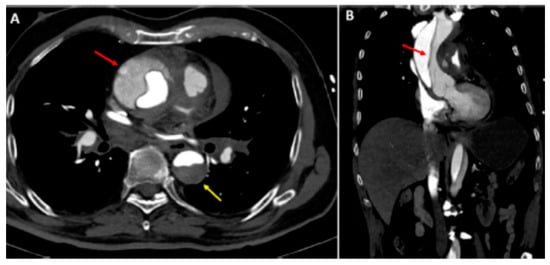

- Mauro, C.; Vriz, O.; Romano, L.; Citro, R.; Russo, V.; Ranieri, B.; Alamro, B.; Aladmawi, M.; Granata, R.; Galzerano, D.; et al. Imaging Cardiovascular Emergencies: Real World Clinical Cases. Heart Fail. Clin. 2020, 16, 331–346. [Google Scholar] [CrossRef] [PubMed]